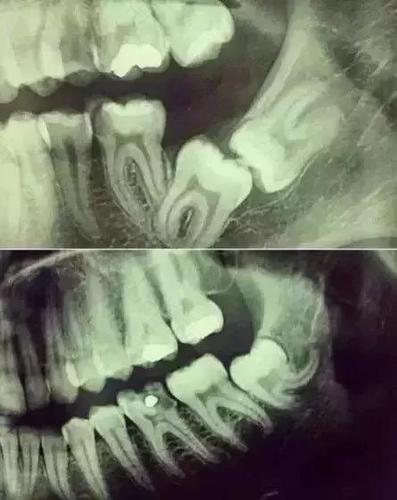

拔牙,听起来就让人毛骨悚然的词语。可有些人不可避免需要面临拔牙这件事,所以即便再害怕,也要迎头前进。不过,一般进行拔牙是可以打麻醉的,但什么情况下才需要打麻醉这需要看患者以及牙齿情况。那么,拔牙时打麻药有副作用吗?

拔牙打麻药是有副作用的。口腔拔牙打麻药是局部麻醉,而且麻醉方式有两种,一是阻滞麻醉,二是浸润麻醉。如果是浸润麻醉,则是往粘膜下注射或者牙周膜注射,局部有毛细血管,进入血液循环的麻醉药是很少的。而阻滞麻醉注射比较深,但退药前需要回抽看是否回血,避麻药进入血管。因此进入血液中的麻醉是很少的,它们很快能够被代谢掉。